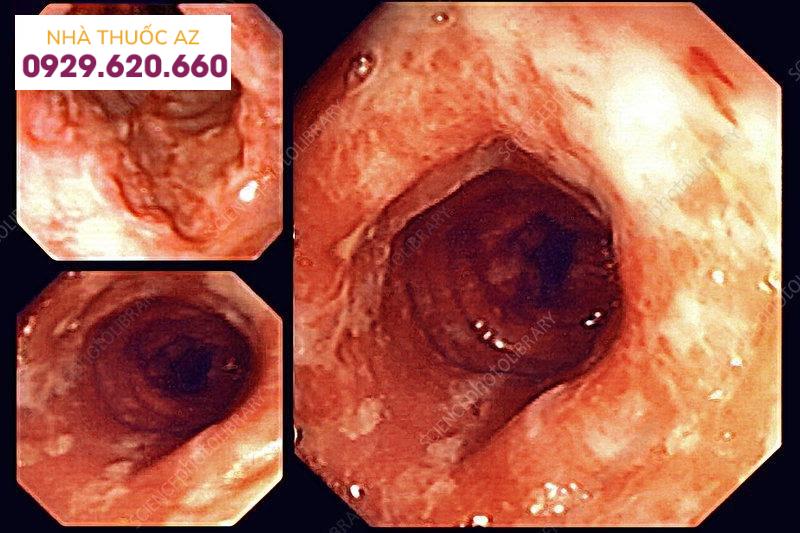

Hình ảnh viêm ruột non

Nội soi viên nang (CE) và nội soi ruột non có thiết bị hỗ trợ (nội soi ruột non có thiết bị hỗ trợ) đã mở rộng đáng kể khả năng chẩn đoán các bệnh ruột non. Nội soi viên nang cung cấp một xét nghiệm không xâm lấn để hình dung toàn bộ niêm mạc ruột non, có thể hỗ trợ chẩn đoán bệnh Crohn ruột non và theo dõi đáp ứng điều trị. Các hạn chế chính của Nội soi viên nang ở bệnh nhân IBD là độ đặc hiệu thấp, thiếu khả năng điều trị và không có khả năng thực hiện sinh thiết.

Hình ảnh viêm ruột non qua nội soi viên nang